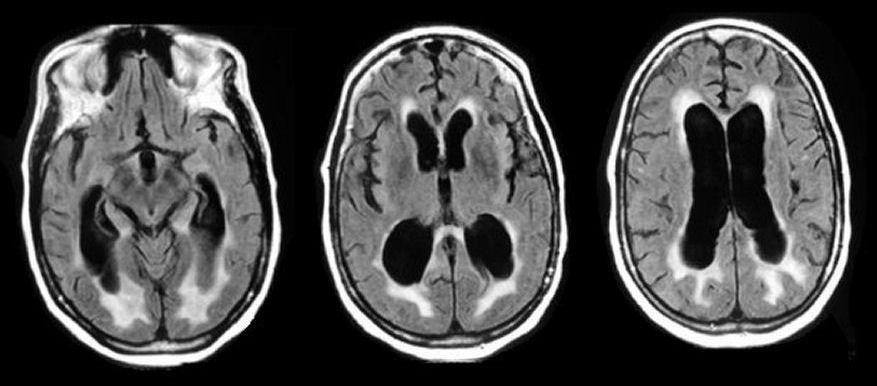

- Ressonância Magnética (RM): método preferencial, revela dilatação dos ventrículos cerebrais (hidrocefalia ventriculomegalia) sem atrofia cortical significativa.

RMN DE ENCÉFALO COM VENTRÍCULOS DILATADOS E EDEMA TRANSEPENDIMÁRIO